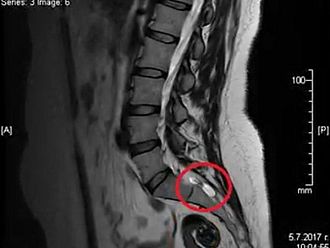

Научната програма стартира с встъпителна лекция на д-р Десислава Стойчева, специалист по образна диагностика. Д-р Стойчева има значителен опит в провеждането на образни изследвания при пациенти с кисти на Тарлов, като акцентът в нейната лекция ще бъде поставен върху възможностите на ядрено-магнитния резонанс на гръбначния стълб за диагностика на това рядко заболяване.